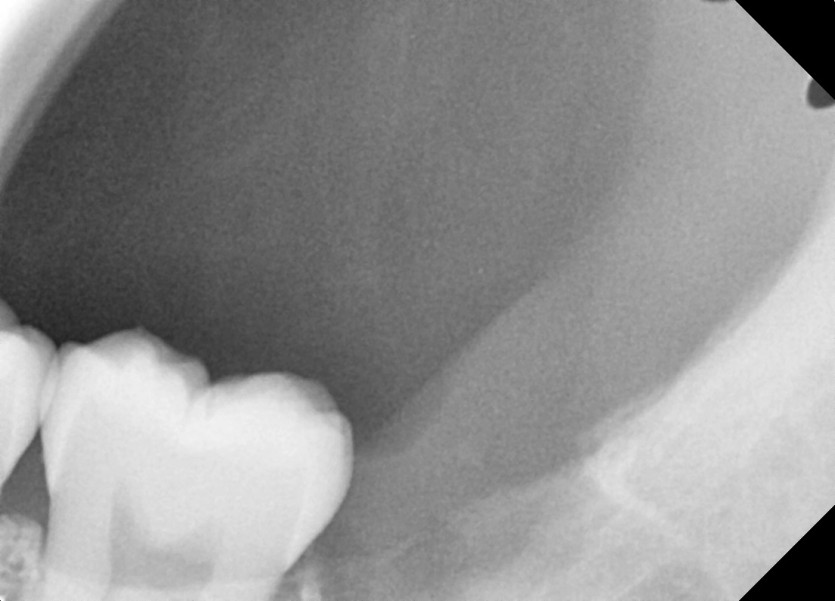

#18,28,38,48 사랑니 발치 (#19과잉치 포함)

구강 외과 전문의가 당일 발치했습니다.